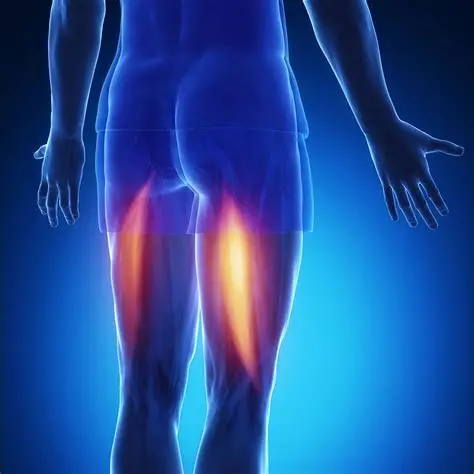

Hamstring Strain